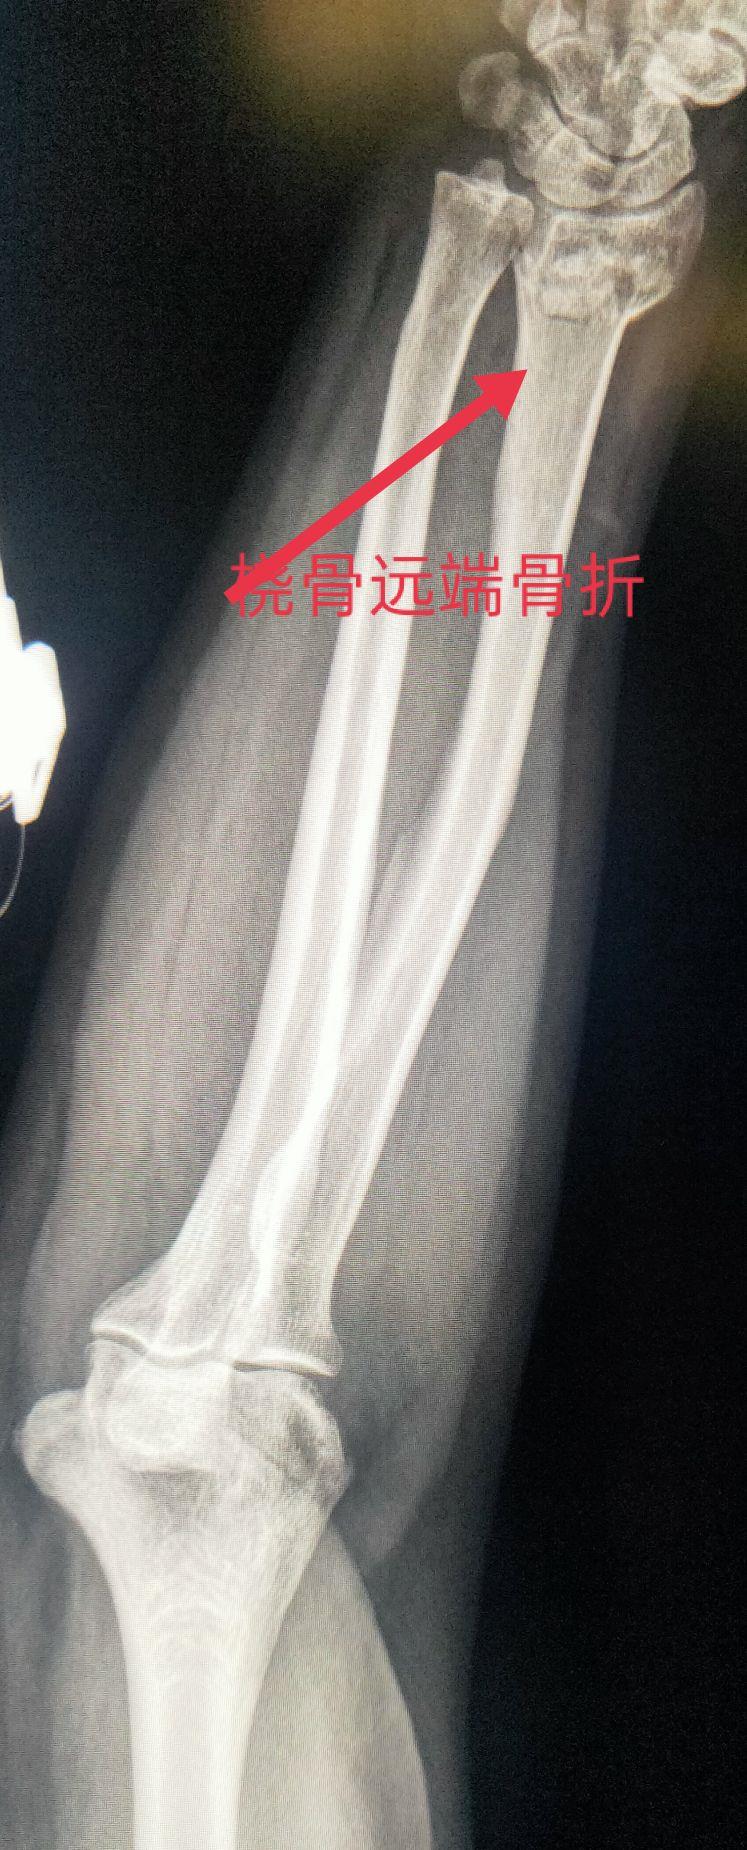

四、尺、桡骨骨折X线片

尺骨桡骨骨折以桡骨远端骨折多见。其次是尺骨桡骨双骨折,多发生于青少年。